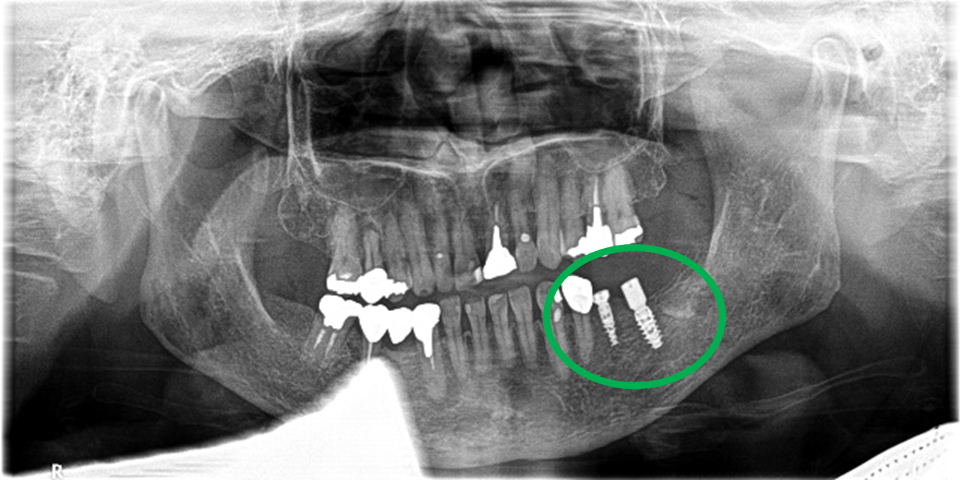

Before

After